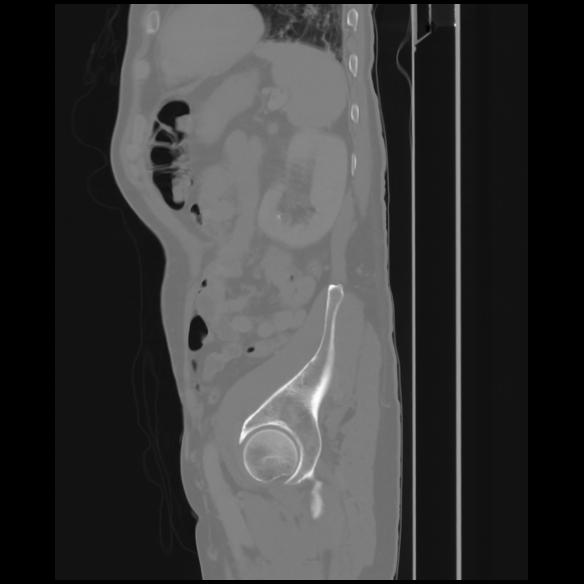

7 CUERPO,CE,Sagittal,3.000,CUERPO,Sagittal,